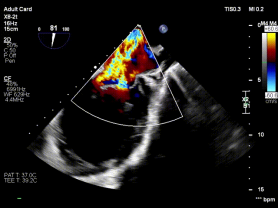

复杂FMR(大GAP):策略性处理实现有效降反流

【图片6:术前超声图】

病例2为复杂功能性二尖瓣反流(FMR),术前影像提示前后瓣叶对合不良,存在明显间隙(GAP),反流程度达极重度。该类病例因瓣叶牵拉明显、张力大,是TEER技术中的典型难点。

针对该病例特点,团队制定个体化诊疗策略,在穿刺位置、器械路径及夹持方式上进行精细设计。术中,团队优化房间隔穿刺高度与位置,匹配GAP结构特点;反复调整导向系统,确保器械垂直对准反流中心;通过多平面及三维TEE确认最佳夹持窗口;采用分步夹持策略,提高瓣叶抓取成功率,确保手术过程平稳。